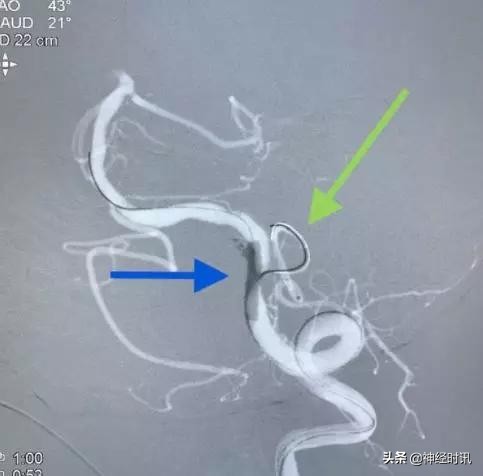

通过几次尝试释放,我们基本摸准了支架头端的定位,然后半释放支架(只保留尾端瘤颈部小部分,箭头),这样可以保证填塞更致密。填入3个Axium弹簧圈后,我们完全释放支架。

换一个角度看:绿色虚线代表颈内动脉边缘,红箭头为支架的显影丝,是不是正好平齐呢?